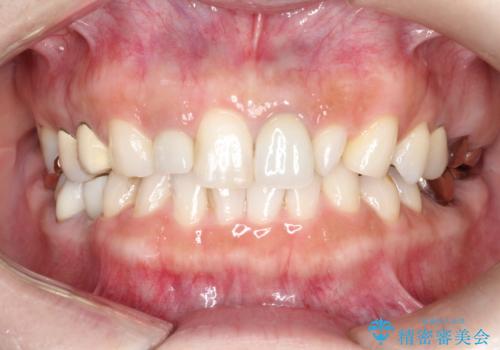

[根管治療・セラミッククラウン] 前歯の痛み・見た目を改善したい

![[根管治療・セラミッククラウン] 前歯の痛み・見た目を改善したいの症例 治療前](https://seimitsushinbi.jp/wp/wp-content/uploads/2021/10/27aece2ee2a0fb95849ae035eabf5926-500x350.jpg?v=1633830098)

![[根管治療・セラミッククラウン] 前歯の痛み・見た目を改善したいの症例 治療後](https://seimitsushinbi.jp/wp/wp-content/uploads/2021/10/969aa8878a18bb42608c420b34b6b67f-500x350.jpg?v=1633830182)